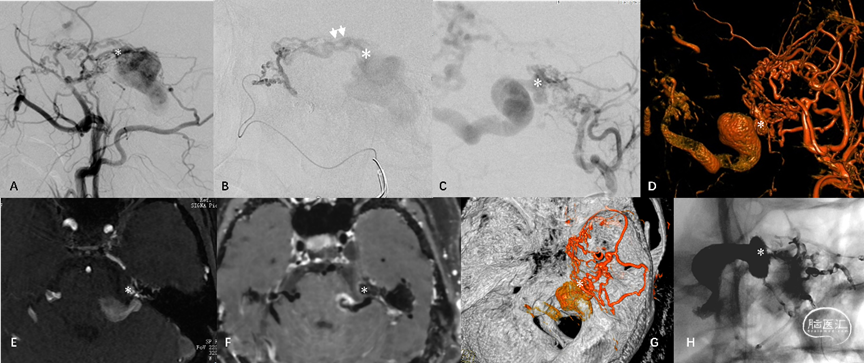

3.板障-导静脉型硬脑膜动静脉瘘(diploic-emissary vein type DAVF, DEV-DAVF),即动-静脉移行起自骨内的板障静脉或穿骨的导静脉,向静脉窦或浅表静脉系统引流。影像学表现为骨内静脉结构早显,并早于静脉窦显影(图4)。

图4. 骨内静脉系统与板障-导静脉型DAVF。板障-导静脉型DAVF,骨内的初级静脉(A白箭)汇聚至板障静脉SP(B双白箭),经蝶顶窦-海绵窦向眼静脉侧裂浅、深静脉逆流(C)。

DAVF的血管构筑包括本中心提出的新分型、Cognard分型、部位、偏侧性、初级静脉结构的位置,伴有静脉流出道梗阻以及与邻近梗阻静脉窦的位置关系。DAVF的偏侧分为左侧、右侧及中线病变。DAVF的位置包括:侧窦区、天幕区(包括天幕缘及天幕内侧)、上矢状窦区、前颅底、窦汇区、髁前区、大脑镰及其他少见部位。DAVF的初级静脉结构包括:(1)硬膜血管汇集区(Shunted pouch, SP);(2)桥静脉硬膜内段;(3)骨内静脉湖。以上结构通过常规血管造影及三维融合成像进行评估,对结构定位不确定时,参考高分辨磁共振(magnetic resonance imaging, MRI)、双容积融合成像辅助定位。以下为不同部位不同类型的硬脑膜动静脉瘘DSA特点。

图15. 侧窦区窦型DAVF典型血管构筑。初级硬膜静脉由脑膜中动脉(MMA)及枕动脉供血,向横-乙交界区血管汇集区(SP)(白箭)汇聚后进入静脉窦,乙状窦内间隔形成(A-C)。天幕岩部硬膜初级静脉向横-乙交界区SP汇集(双白箭),枕动脉血供经乙状窦垂直段SP(白箭头)进入静脉窦,并伴有上矢状窦(SSS)后部血栓形成(D-F)。DAVF经乙状窦颈静脉孔区SP(双白箭头)进入静脉窦并逆流,伴有乙状窦颈静脉孔段闭塞(G-I)

图16. 侧窦区桥静脉型DAVF典型血管构筑。MMA(白箭)、脑膜后动脉(双白箭)、大脑中动脉硬膜支(白箭头)及大脑后动脉硬膜支(黑双箭头)向Labbe桥静脉硬膜内段汇集(A-C)。MMA与颈内动脉(ICA),MMA与椎动脉,MMA与咽升动脉分别行双容积融合成像(D-F)。经动脉栓塞后Onyx胶在桥静脉及软膜静脉起始部的铸型(G)

图 17. 天幕缘组DAVF典型血管构筑。A-D:ECA发出的供血分支向天幕缘桥静脉(星号)汇集,经扩张的桥外侧静脉向对侧同名静脉引流。颌内动脉超选择造影(B)显示翼管动脉管径增粗,移行为硬膜静脉结构(双白箭)再汇入共同静脉端。F-G:TOF及增强磁共振、DAVF与颅骨的双容积融合成像显示桥静脉起始部(星号)位于岩尖的天幕游离缘。G:TAE后Onyx胶在桥静脉起始部的铸型

图 18. 上矢状窦区桥静脉型DAVF典型血管构筑。A-B:双侧MMA(单、双箭)向大脑上静脉桥静脉汇集。C:TAE后Onyx胶在硬膜动脉网(单、双箭)及桥静脉(双白箭头)的铸型。D:患者合并SSS中部血栓

图19. 髁前区DAVF典型血管构筑。A-C:枕动脉、咽升动脉供血分支向颈静脉结节静脉丛(JTVC)(白箭)汇集,经岩下窦向海绵窦、侧裂浅静脉逆流。D:ECA主干与咽升动脉双容积融合成像。E:位于骨内的JTVC(白箭)是髁前区板障-导静脉型DAVF的初级静脉结构。F:术中利用微导丝与静脉双容积融合成像定位。G-H:TVE闭塞JTVC及髁前静脉,治愈性栓塞DAVF同时保护岩下窦